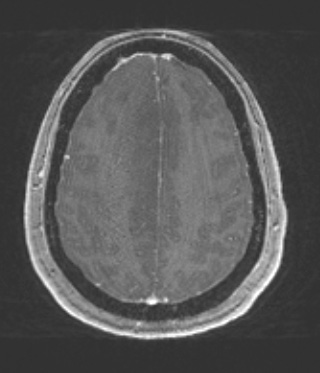

Washington University Experience | NEOPLASMS (GLIAL) | Astrocytoma, IDH-mutant, WHO Grade 2 | 8A2 (Case 8) T1W - Copy

The T1-weighted contrast administered image is hypointense and fails to enhance with contrast.